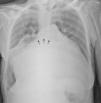

A radiografia torácica mostrou cardiomegalia acentuada (índice cardiotorácico 0,92), alargamento do ângulo da carina e elevação dos brônquios principais (Figura 1).

A AEG define‐se por um diâmetro ântero‐posterior ≥8cm num ecocardiograma ou se numa radiografia de tórax atingir a parede lateral direita da caixa torácica. Associa‐se à doença mitral reumática, em particular à insuficiência mitral grave pelo que raramente é assintomática. Os sintomas devem‐se à valvulopatia de base podendo ainda resultar de compressão esofágica ou das vias respiratórias e de eventos tromboembólicos. A sua aparência radiográfica pode confundir‐se com derrame pleural/pericárdico ou com uma neoplasia havendo casos descritos de «toracocentese» e «biópsia» da AEG. O seu diagnóstico torna‐se, portanto, essencial para a prevenção de eventuais complicações iatrogénicas.